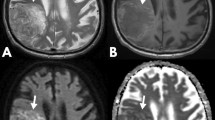

Ours is a quaternary neurosurgical centre; therefore the standard (structural and DWI) MRI sequences in this study originated from 10 different referring institutions (institution 1 to institution 10): 29 from our own institutions, 4 from institution 2, 3 from institution 3, 2 from institution 4, and one each from the remaining six institutions. The studies were acquired on 18 different scanners (31 at 1.5 Tesla, and 13 at 3 Tesla) from all major vendors: four General Electric scanners [Discovery MR450 (number of patients n = 5), 2× Signa Excite (n = 1 each), Genesis Signa (n = 2)], seven Siemens scanners [3× Avanto (n = 7, n = 2, n = 1), a Trio (n = 9), Symphony (n = 4), Skyra (n = 3), Espree (n = 1)], six Philips scanners [Ingenia (n = 2), 5× Achieva (n = 1 each)] and one Toshiba scanner (n = 1). All acquisitions included axial T2-weighted images, and axial standard 3-directional whole brain DWI. The median [min, max] values of the parameters of the T2-weighted images were echo time (TE) = 99.5 [80, 141] ms; repetition time (TR) = 4610 [2500, 7480] ms, in-plane resolution = 0.5 × 0.5 [0.3 × 0.3, 0.9 × 0.9] mm2; slice thickness = 5 [1, 6] mm; gap between slices = 1.5 [0, 2] mm. All DWI acquisitions included diffusion gradient weighting values b = 0 s/mm2 and b = 1000 s/mm2; the median [min, max] of other parameters were TE = 90.5 [69.5, 137] ms; TR = 4000 [2837, 10,000] ms, in-plane resolution = 1.25 × 1.25 [0.5 × 0.5, 2.5 × 2.5] mm2; slice thickness = 5 [4, 6] mm; gap between slices = 1.5 [0, 2] mm. For each patient, the imaging study was performed on average (standard deviation, sd) 2.3 (2.8) months prior to the tissue diagnosis. Image examples for the glioma molecular subgroups are shown in Fig. 2.